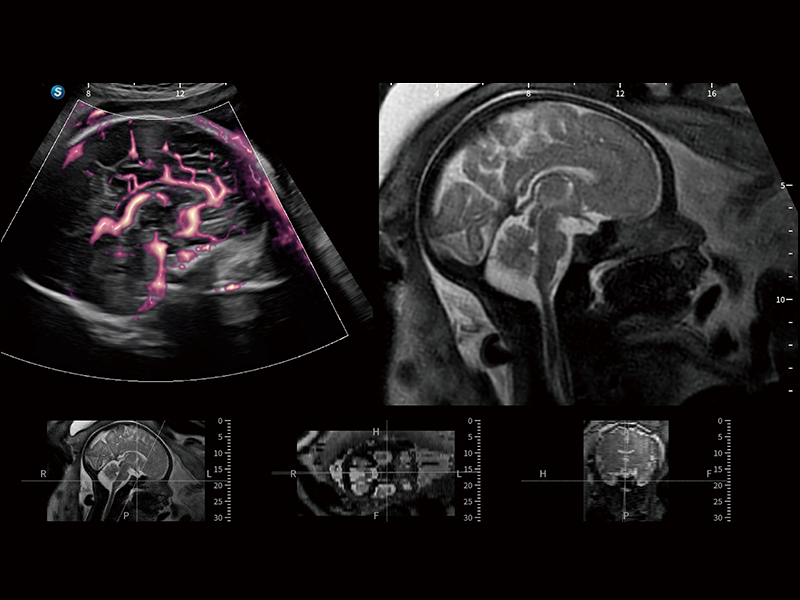

在传统血流的基础上优化扫查和算法策略,能够更好的抑制组织信息,提炼红细胞运动信息,得到更高帧频,高灵敏度和分辨率的血流信号,还原更真实的血流动力学。

通过光照模型,使二维血流显示出立体的效果,增加血流的敏感性、成束性,减少外溢。可以和其他不同的血流技术联合使用,融合不同技术的优势。轻松应对微小血管,增强血流的立体效果,提升视觉敏感性。

通过创新的Matrix E自适应滤波算法,能有效滤除软组织和噪声信号,最大限度保留超低速微细血流的信号;结合超长时间域算法,极大提升细微血流的敏感性和空间分辨率,更真实的反应组织、包块的血流灌注情况。